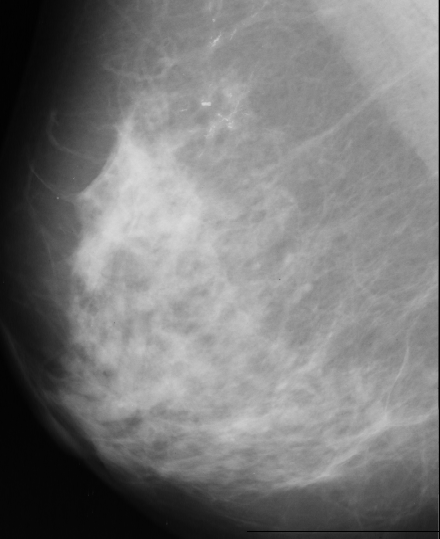

Input:Given an image for example of industrial image of object with holes or such as a mammogram with the presence of microcalcifications of different size and shape (which can be introduced by simulation for the purpose of the project).

Microcalcifications are tiny specks of calcium in the breast. These minute calcifications are usually found in an area of rapidly dividing cells. When many microcalcifications are seen in one area, they are referred to as a cluster and may indicate a small cancer. About half of the cancers detected by mammography appear as a cluster of microcalcifications.

We have used images from http://peipa.essex.ac.uk/ipa/pix/mias/. The images were downloaded from the MIAS MiniMammographic Database, that were digitized at 200µm (the original MIAS Database is digitised at 50µm), with every image being 1024 pixels x 1024 pixels. Tipical mammograms used for image processing are digitized at 35µm-70µm and 4096 gray levels (12 bits), while we worked with mammograms digitized at 200µm with 256 gray levels (8 bits) because of disk space. The use of these low-resolution images caused the disappearance of some microcalcifications that were present in the original images (digitized at 50µm).